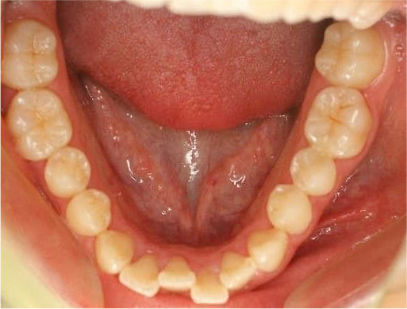

症例03

前歯が咬み合ってなく開咬の症例

上下の前歯が咬んでない事と前歯のデコボコを主訴として来院されました。

通常通り検査を行い「前歯部にデコボコを伴う開咬」と診断されました。

治療計画

舌の悪習癖のために上顎の歯並びの幅が狭いために裏側から拡大し、その後、上顎には裏側に下顎には表側に矯正装置を装着して綺麗に歯を並べてまた咬み合わせも改善しました。

矯正の種類

上は裏側に、下は表側にセラミック(白い矯正装置)

• 下側